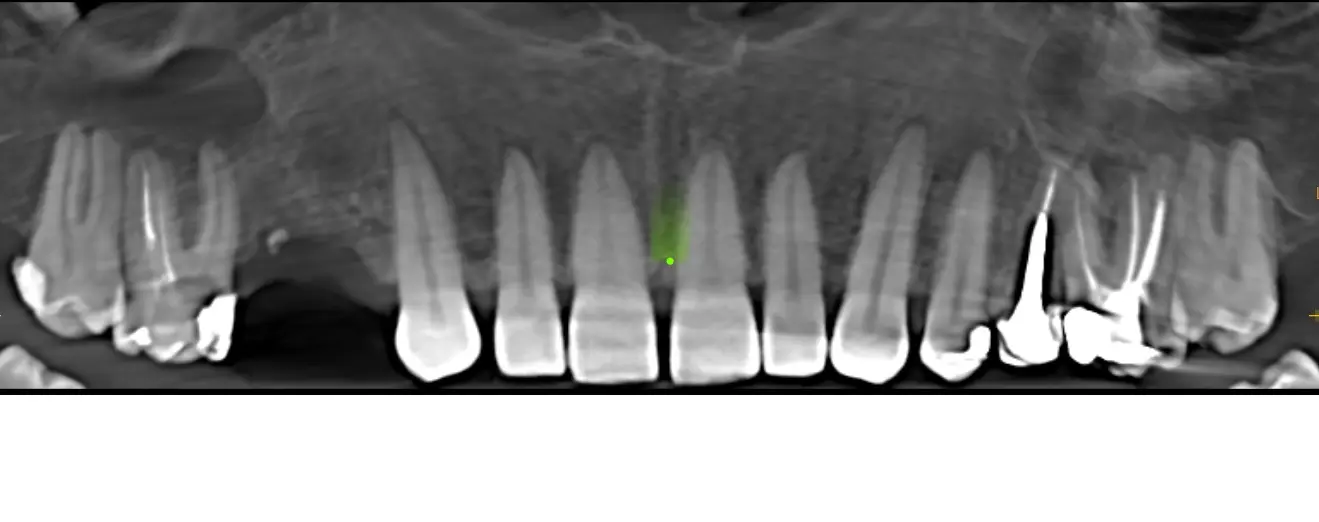

Al realizarle la tomografía se evidencia de manera general dientes con tratamientos de conductos que no llelgan al limite CDC (Ver imagen 1 panorámica). En zona de Pd 16 se ve imágen hipodensa , de carácter expansivo que empuja las zonas adyacentes y el seno maxilar, generando una disminución del reborde óseo tanto palatino como vestibular, se observa que la pieza dental 16 presenta tratamiento de conducto, esta lesión genera también un engrosamiento de la membrana sinusal (posible quiste de retención mucosa) y disminución o posible ausencia del piso sinusal. Sobre la misma se observa en la imagen N°6 que presenta los cortes trasnaxiales, una cavidad de aire en dicho quiste periapical. Posiblemente debido a una interacción con las bacterias sinusales. En la cavidad sinusal se observa el pólipo sinusal de la cavidad derecha.